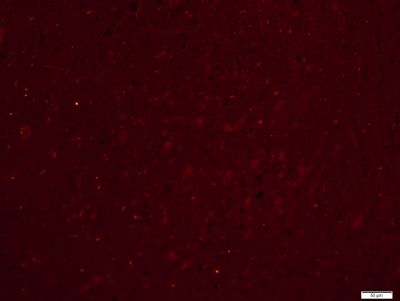

5-羟色胺受体2A免疫组化荧光抗体

产品应用WB=1:500-2000 ELISA=1:500-1000 IHC-P=1:400-800 IHC-F=1:400-800 Flow-Cyt=3ug/Test IF=1:200-800 (石蜡切片需做抗原修复)